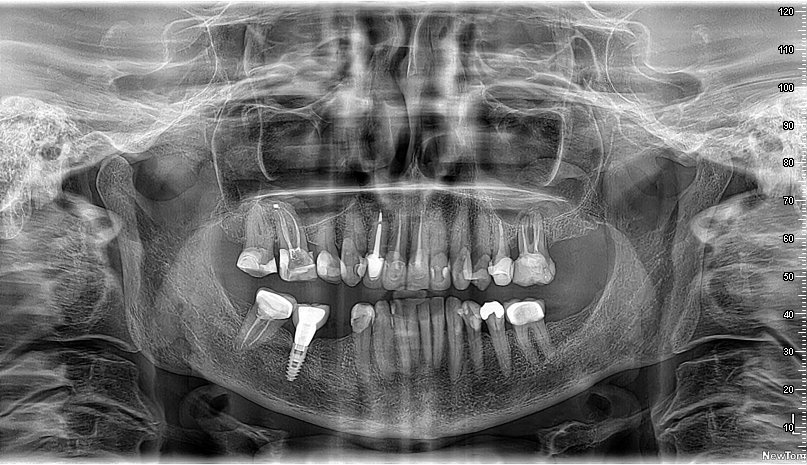

Imágenes 2D-3D Radiografías, Tomografías DENTAL, ATM, SPN, OIDO

Nuestra tecnología Cone Beam 3D permite visualizar estructuras óseas y dentales con alta definición, favoreciendo diagnósticos exactos y resultados clínicos confiables.

"Trabajo con TAC Facial para todos mis pacientes que requieren estudios de implantes. Las imágenes son claras, precisas y la entrega es muy rápida. Definitivamente aporta seguridad al diagnóstico."

Dr. Marcelo M.

Implantólogo